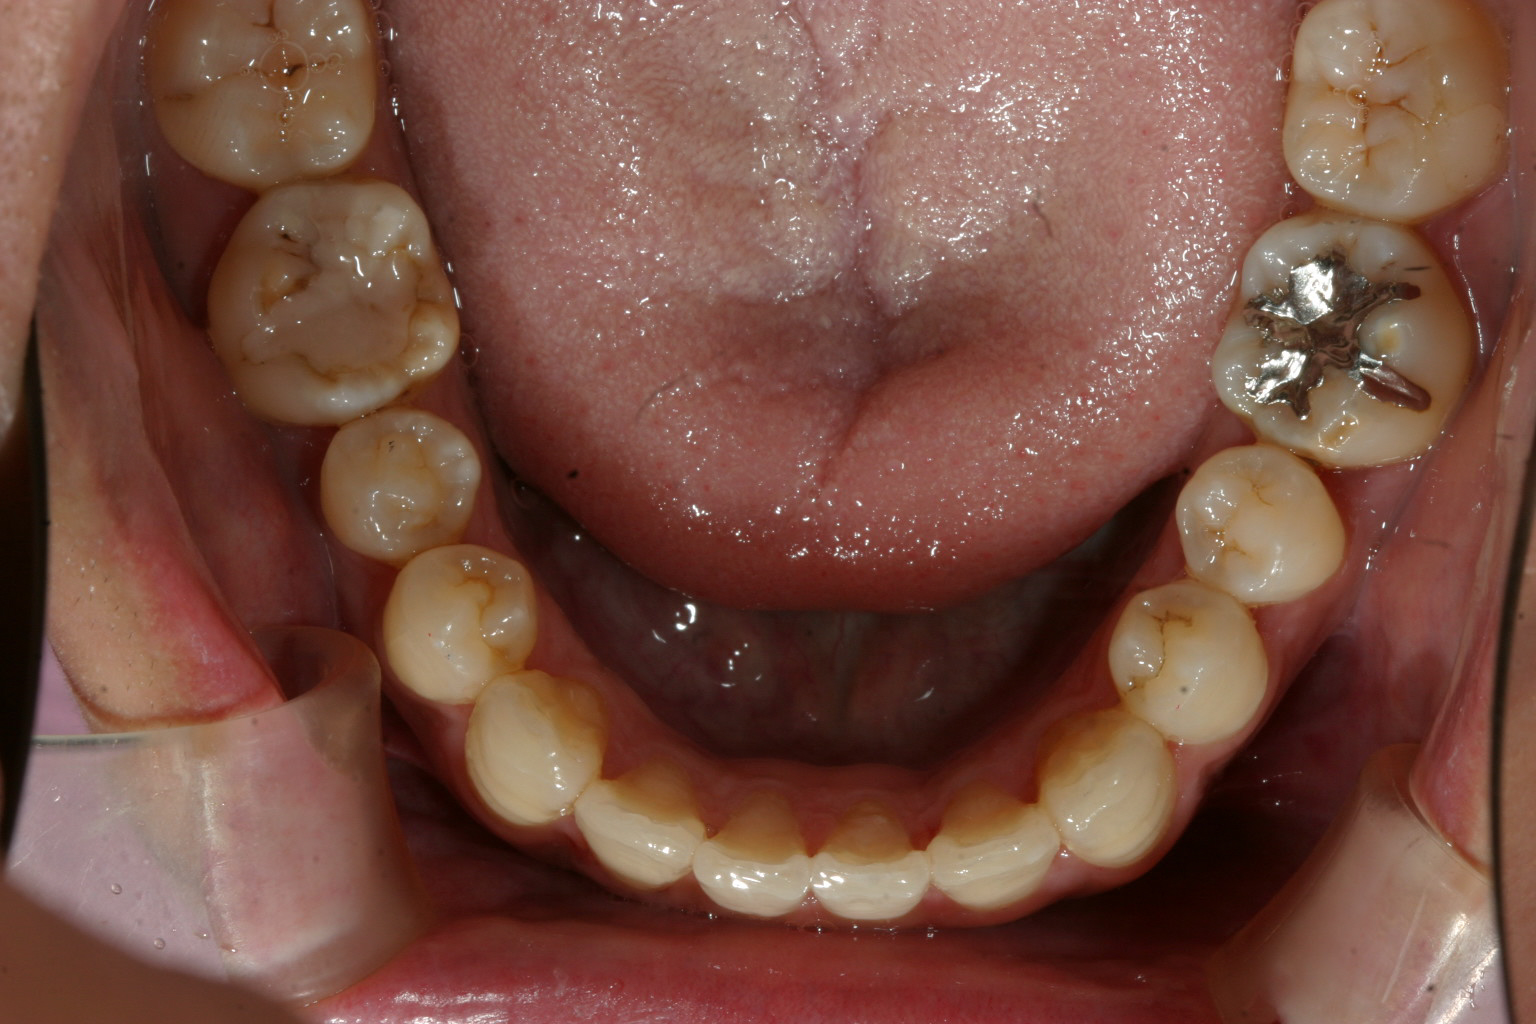

上顎1番が鳥の翼のように反転してますね~この様な症状を翼状捻転って言います。

下顎の症状は軽度ですね~